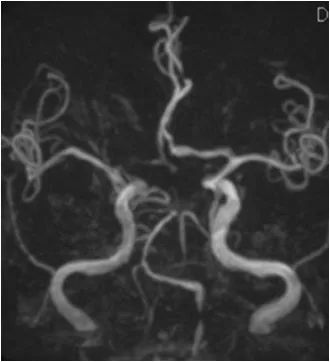

MRA:双侧胚胎型大脑后动脉;左椎动脉优势,V4段重度狭窄(图2)。

图2

DSA:右颈内动脉C6段重度狭窄;双侧胚胎型大脑后动脉;左椎动脉V1段迂曲,V4段重度狭窄;右椎动脉纤细,V4段以远显影欠佳(图3-6)。